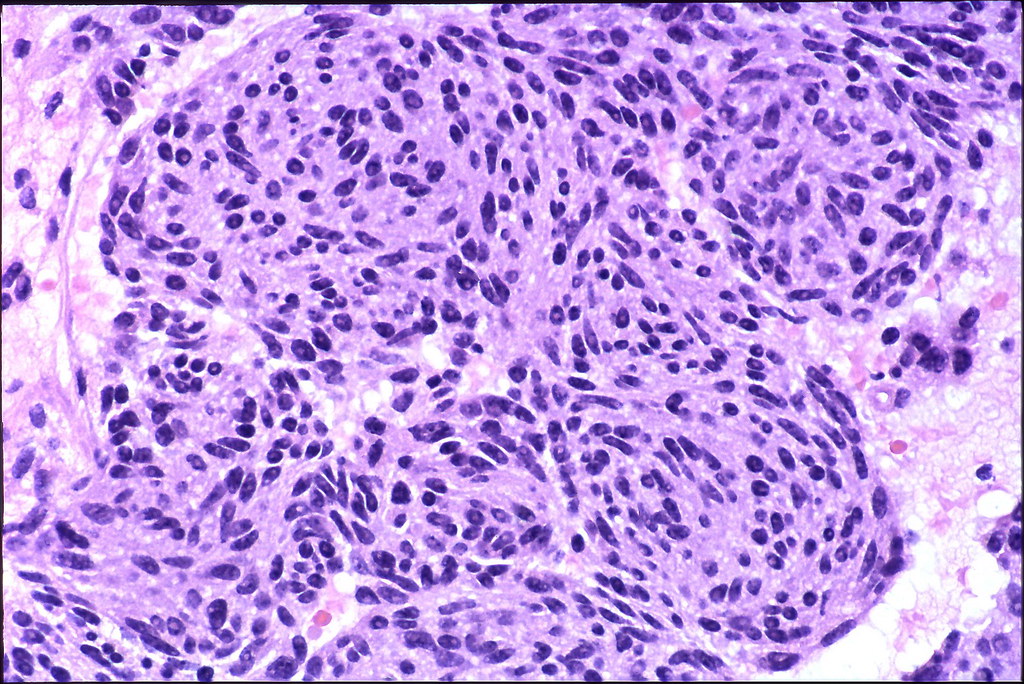

Microphotograph showing a spindle cell lesion; cells being arranged in Spindle Cell In Pathology Spindle cells may be focally positive to epithelial markers such as cytokeratin, ema (36%), and cd68 (25%). Cutaneous spindle cell neoplasms are relatively common and present surgical pathologists with diagnostic challenges. They are found both in normal, healthy. Spindle cell neoplasms can affect the oral cavity. In the oral cavity, the origin of the spindle cell neoplasms may be traced. Spindle Cell In Pathology.